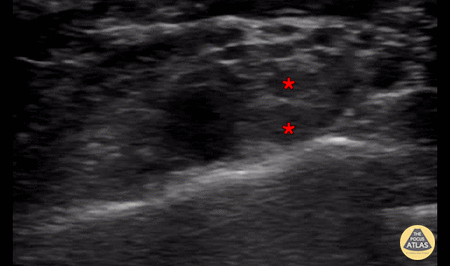

In-plane interscalene block, with needle entering from screen right (lateral and posterior), showing injection of anesthetic within the interscalene groove, surrounding the brachial plexus (*). The subclavian artery can be seen pulsating screen left (medial) to the brachial plexus. Denver Health Ultrasound Fellowship Archive